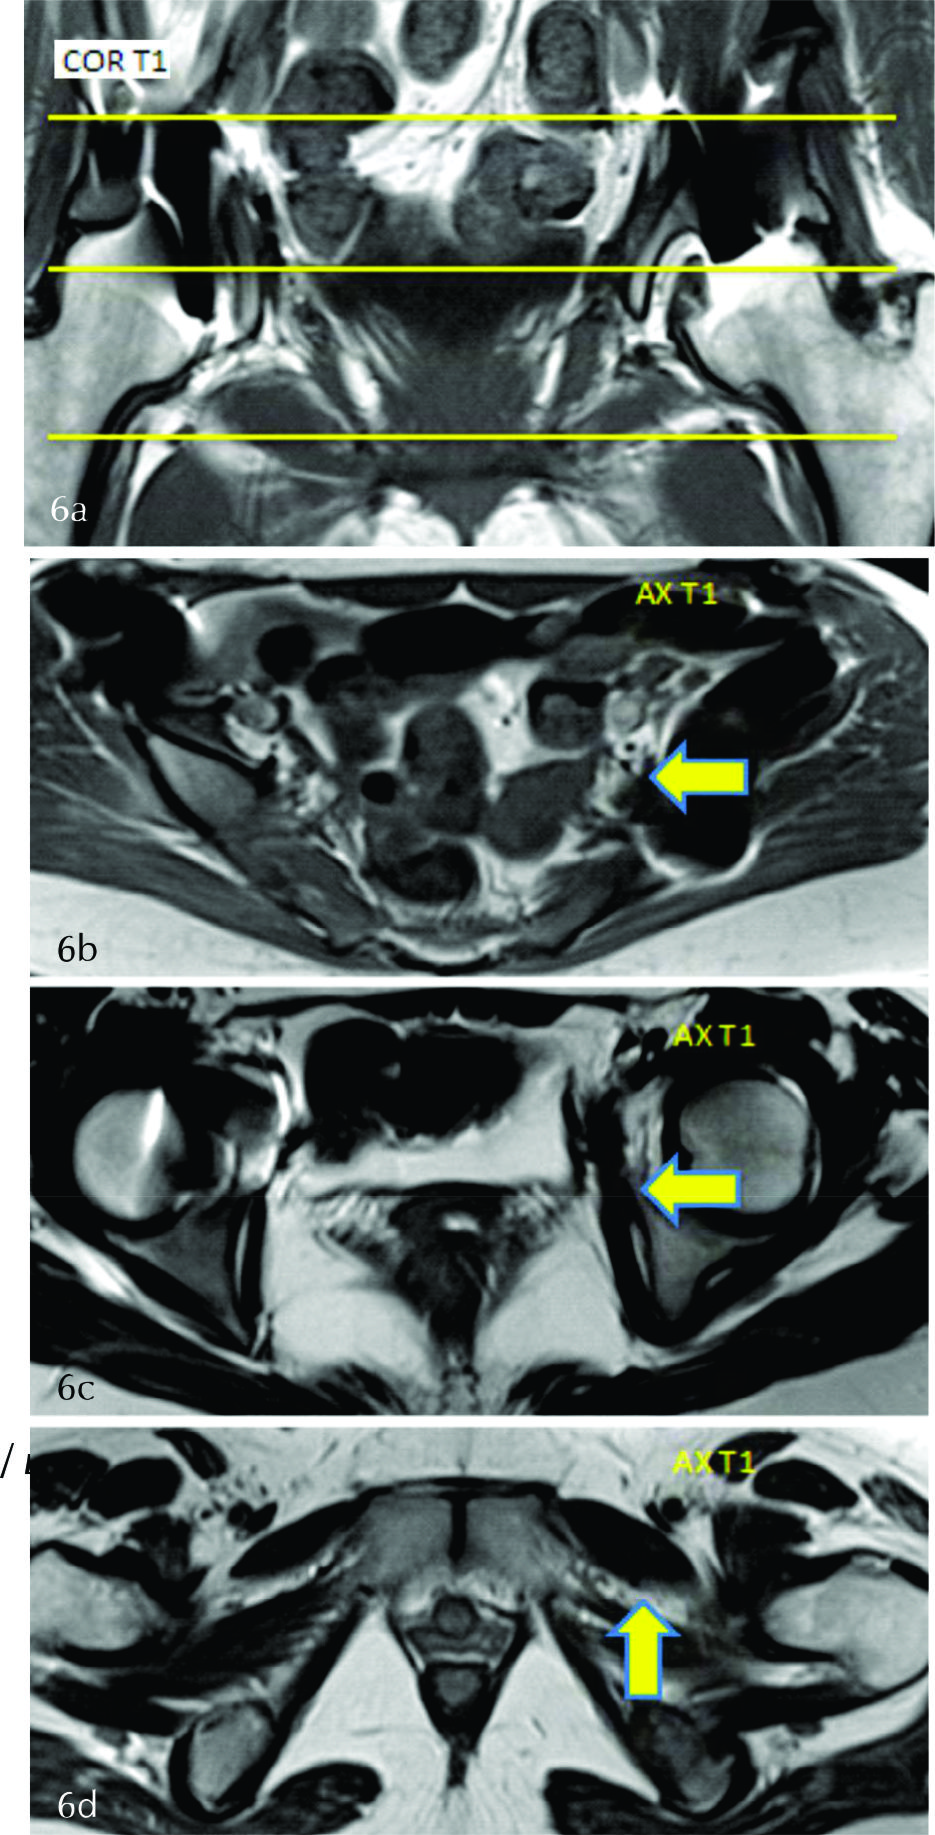

En la figura 6 se muestra la topografía del nervio obturador.

Figura 6

Topografía del nervio obturador: en la imagen coronal se observan líneas horizontales amarillas que muestran la referencia de los cortes axiales en los cuales se muestra el trayecto del nervio obturador (flechas).